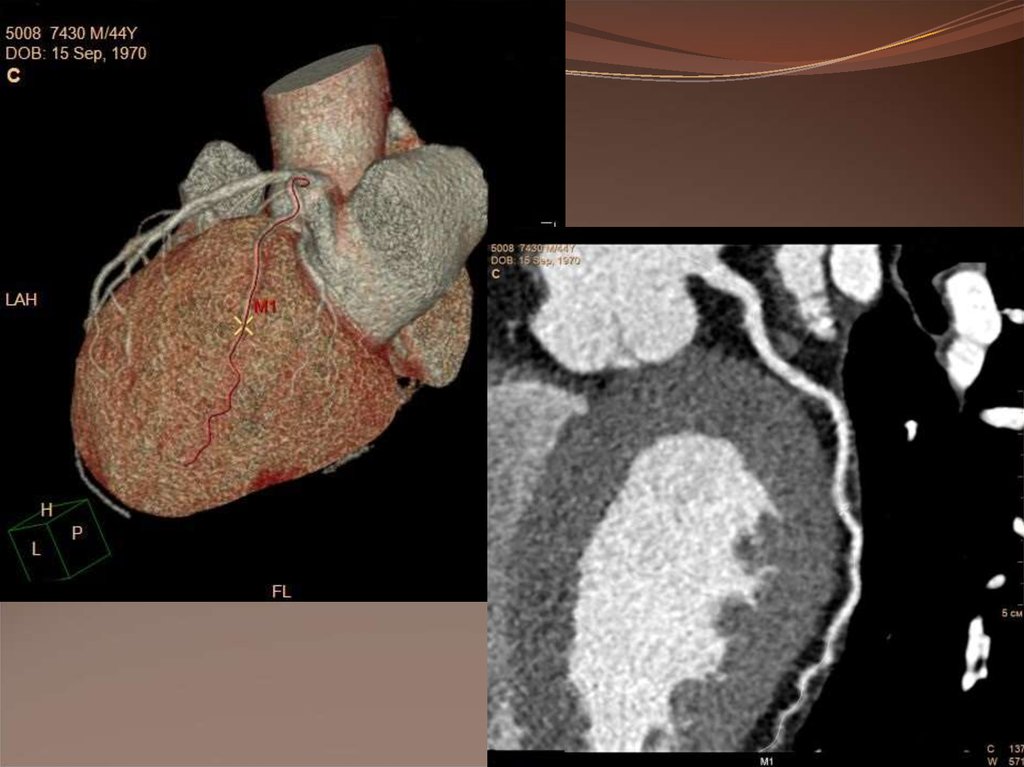

Компьютерная томография коронарных

артерий.

Методика основана на внутривенном введении

йодсодержащего контрастного препарата с последующим

отслеживанием его прохождения по коронарному руслу при

одновременной записи ЭКГ и последующей математической

обработкой полученных изображений.

Построение трехмерной реконструкции